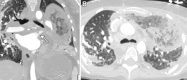

As lung transplantation has become the most effective definitive treatment option for end-stage chronic respiratory diseases, yearly rates of this surgery have been steadily increasing. Despite improvement in surgical techniques and medical management of transplant recipients, complications from lung transplantation are a major cause of morbidity and mortality. Some of these complications can be classified on the basis of the time they typically occur after lung transplantation, while others may occur at any time. Imaging studies, in conjunction with clinical and laboratory evaluation, are key components in diagnosing and monitoring these conditions. Therefore, radiologists play a critical role in recognizing and communicating findings suggestive of lung transplantation complications. A description of imaging features of the most common lung transplantation complications, including surgical, medical, immunologic, and infectious complications, as well as an update on their management, will be reviewed here. Keywords: Pulmonary, Thorax, Surgery, Transplantation Supplemental material is available for this article. © RSNA, 2021.